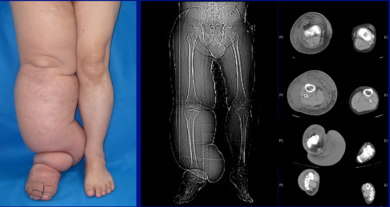

| Lower extremity lymphedema | |

The most common manifestation of lymphedema is soft tissue swelling, edema. As the disorder progresses, worsening edema and skin changes including discoloration, verrucous (wart-like) hyperplasia, hyperkeratosis, papillomatosis, dermal thickening, and ulcers may be seen. Additionally, there is increased risk of infection of the skin, known as Erysipelas.

Diagnosis is generally based on signs and symptoms, with testing used to rule out other potential causes.[2] An accurate diagnosis and staging may help with management.[2] A swollen limb can result from different conditions that require different treatments. Diagnosis of lymphedema is currently based on history, physical exam, and limb measurements. Imaging studies such as lymphoscintigraphy and indocyanine green lymphography are only required when surgery is being considered.[2] However, the ideal method for lymphedema staging to guide the most appropriate treatment is controversial because of several different proposed protocols.[29][30] Lymphedema can occur in both the upper and lower extremities, and in some cases, the head and neck. Assessment of the extremities first begins with a visual inspection. Color, presence of hair, visible veins, size and any sores or ulcerations are noted. Lack of hair may indicate an arterial circulation problem.[31] Given swelling, the extremities' circumference is measured for reference as time continues. In early stages of lymphedema, elevating the limb may reduce or eliminate the swelling. Palpation of the wrist or ankle can determine the degree of swelling; assessment includes a check of the pulses. The axillary or inguinal nodes may be enlarged due to the swelling. Enlargement of the nodes lasting more than three weeks may indicate infection or other illnesses such as sequela from breast cancer surgery requiring further medical attention.[31]

Chronic venous stasis changes can mimic early lymphedema, but the changes in venous stasis are more often bilateral and symmetric. Lipedema can also mimic lymphedema, however lipedema characteristically spares the feet beginning abruptly at the medial malleoli (ankle level).[2] As a part of the initial work-up before diagnosing lymphedema, it may be necessary to exclude other potential causes of lower extremity swelling such as kidney failure, hypoalbuminemia, congestive heart-failure, protein-losing nephropathy, pulmonary hypertension, obesity, pregnancy and drug-induced edema.[citation needed]

- Stage 3: Swelling is irreversible and usually the limb(s) or affected area becomes increasingly large. The tissue is hard (fibrotic) and unresponsive; some patients consider undergoing reconstructive surgery, called "debulking". This remains controversial, however, since the risks may outweigh the benefits and the further damage done to the lymphatic system may in fact make the lymphedema worse.

- Stage 4: The size and circumference of the affected limb(s) become noticeably large. Bumps, lumps, or protrusions (also called knobs) on the skin begin to appear.

- Stage 5: The affected limb(s) become grossly large; one or more deep skin folds is prevalent among patients in this stage.